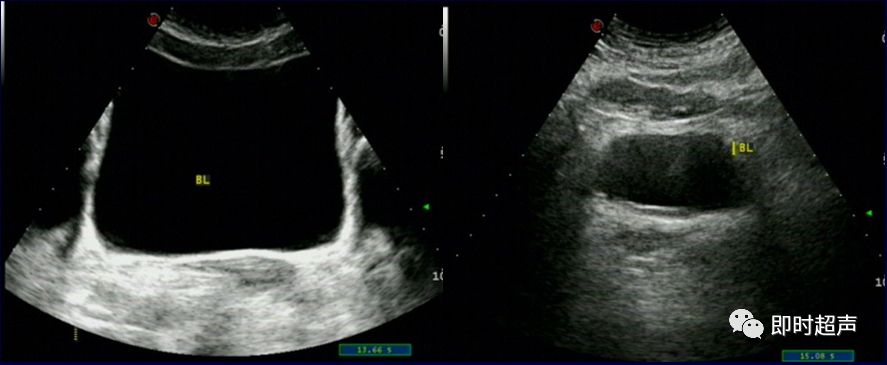

正常膀胱超声图像(经腹)

膀胱的形态大小、位置均与尿量有关

充盈良好 充盈差

膀胱充盈好 膀胱充盈差

患者适当饮水,充盈膀胱,一般容量在300-400ml